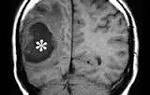

Есть небольшой шанс, что специалист обнаружит синдром дауна на узи. К ним относятся увеличение объема кожи в области затылка, уменьшение размера бедра или кисты в головном мозге. По словам врачей, синдром дауна по узи нельзя диагностировать. Это обследование не выявит ожидаемый риск трисомии 21.

1 Ультразвук плода с большим пузырем 2 Увеличенный NT и отсутствующая носовая кость у плода в 11 недель с синдромом Дауна

Эхопризнаки синдрома дауна на узи, которые указывают на повышенный риск, когда наблюдаются во втором триместре беременности.

Плод с синдромом дауна может иметь небольшую или отсутствующую носовую кость, большие желудочки мозга, толщину затылочной складки и ненормальную правую подключичную артерию.